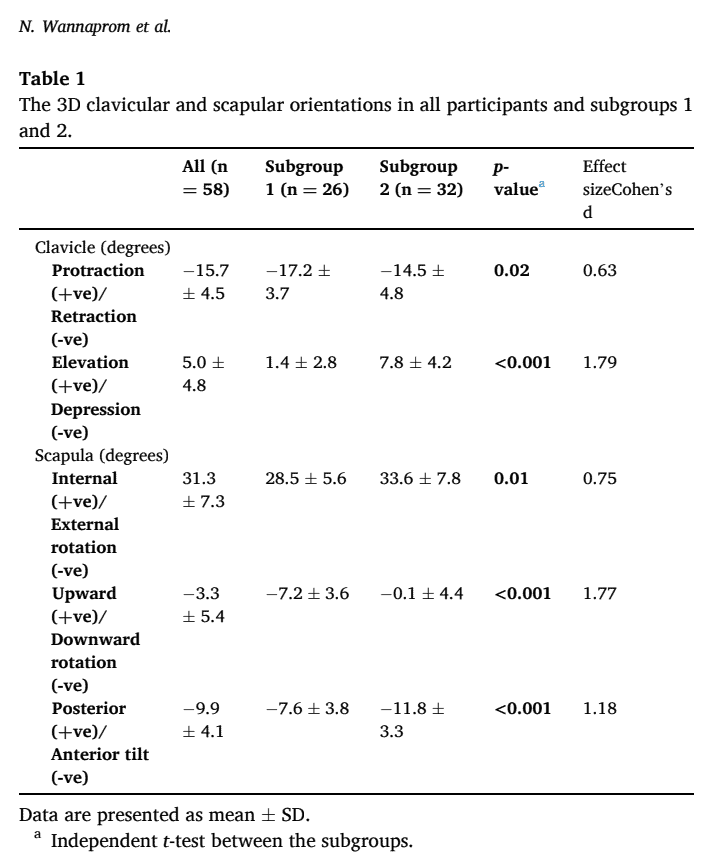

Auf der Grundlage der 3D-Messungen wurden zwei Untergruppen ermittelt. In der Untergruppe 1 zeigten die Teilnehmer eine stärkere Klavikularretraktion und eine Skapularrotation nach unten. In der Untergruppe 2 war das Schlüsselbein stärker angehoben und das Schulterblatt stärker nach vorne gekippt und nach innen gedreht. Die Untergruppe 1 berichtete häufiger über Kopfschmerzen und mehr Schmerzen im oberen oder ganzen Nacken, während die Teilnehmer der Untergruppe 2 mehr Schmerzen im unteren Nackenbereich angaben. Bei allen anderen Ergebnissen (demografische Daten, Intensität, Dauer und Behinderung der Nackenschmerzen) waren die Untergruppen gleich.

Was die Reaktion auf die Skapulierumlagerung bei Nackenschmerzen betrifft, so ergab diese Studie, dass 88,5 % der Teilnehmer in Untergruppe 1 positiv reagierten, während 81,2 % in Untergruppe 2 nicht reagierten.

Rede mit mir über Nerds

In dieser Studie wurden bei Patienten mit chronischen Nackenschmerzen auf der Grundlage von 3D-Messungen der Skapulaausrichtung 2 verschiedene Untergruppen identifiziert. Die Gruppe, die eine stärkere Abwärtsrotation des Schulterblatts und eine Retraktion des Schlüsselbeins aufwies, sprach auf die Umlagerung des Schulterblatts an, während die Gruppe, die eine stärkere Anhebung des Schlüsselbeins, eine Innenrotation und eine anteriore Neigung des Schulterblatts aufwies, bei Nackenschmerzen nicht auf die Umlagerung des Schulterblatts ansprach. Außerdem hatten diejenigen, die auf die Behandlung ansprachen, mehr Schmerzen im oberen Nackenbereich und Kopfschmerzen, während diejenigen, die keine gute Reaktion zeigten, mehr Schmerzen im unteren Nackenbereich hatten. Dies kann eine wichtige Rolle bei der Auswahl Ihrer Behandlungsoptionen für diese Patienten spielen.